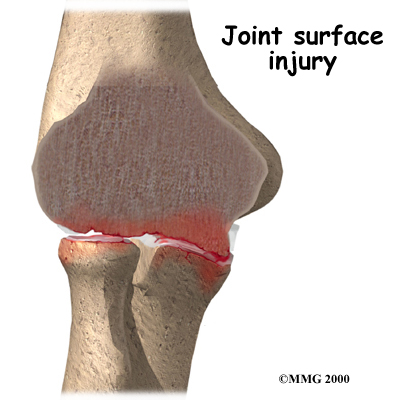

A bad sprain or fracture can damage the articular cartilage. The cartilage can also be bruised when too much pressure is put on the cartilage surface. In some cases OA may be idiopathic which means there isn’t a known reason for the condition, but most of the time, elbow OA is linked with excess use of the arm or a previous injury.

At the time of injury the cartilage surface may not look any different if it has not been directly injured. The injury to the cartilage often doesn't show up until months later. In some cases, however, the damage to the cartilage with the initial injury is severe. Pieces of the cartilage can actually be ripped away from the bone and these pieces do not grow back. Usually they must be surgically removed otherwise they cause problems with the functioning of the joint. If the pieces aren't removed, they may float around in the joint, causing it to catch. These pieces are referred to as loose bodies or joint mice. In addition to catching in the joint they can also cause a lot of pain and do more damage to the joint surfaces if left inside the joint.

Unfortunately the human body does not do a good job of repairing these holes in the cartilage surface of joints. The holes fill up with scar tissue. Scar tissue is not as slick or rubbery as the articular cartilage so the joint mechanics suffer.

Unfortunately the human body does not do a good job of repairing these holes in the cartilage surface of joints. The holes fill up with scar tissue. Scar tissue is not as slick or rubbery as the articular cartilage so the joint mechanics suffer.

Pain and stiffness are the main symptoms of OA of any joint, including the elbow. At first, the pain comes only with activity. Most of the time the pain lessens while doing the activity, but after resting for several minutes pain and stiffness increase. As the condition worsens, you may feel pain even when resting. The pain may interfere with sleep.

You may have swelling around your elbow. Your elbow joint may fill with fluid and feel tight, especially after using it. If the OA is to the stage where all the articular cartilage is worn off the joint surface, you may begin hearing a squeak and feel a creak in the joint when you move your elbow. This creaking sound or sensation is called crepitus.

OA eventually affects the elbow's motion. The elbow joint is one of the most sensitive joints in the body to injury. It quickly becomes stiff and loses motion. The first thing most people notice is that it becomes hard to completely straighten the arm. Later they find it hard to bend.

Loss of motion leads to weakness and decreased function. Carrying heavy objects at the side of the body with the elbow straight is especially difficult.